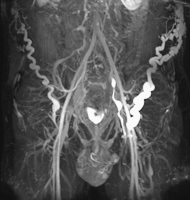

MR-Phlebographie

Abbildung 1: MR-Phlebographie eines 25-jährigen Patienten mit schwerem postthrombotischen Syndrom und Obstruktion der infrarenalen V. cava sowie Beckenvenenstrombahn bds. Der venöse Abstrom erfolgt über zahlreiche Kollateralvenen der Bauchwand bzw. des Beckens.